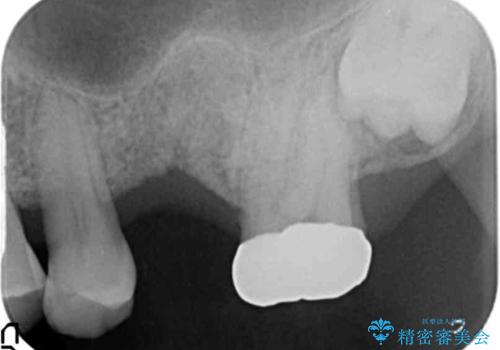

- 奥歯のインプラントをご希望し、来院された患者様です。

精査したところ上顎骨の厚みが薄かったため、ソケットリフト(上顎洞底挙上術)を併用してインプラント治療を行いました。